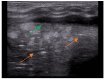

Lung ultrasound (LUS) is, at present, a standard technique for the diagnosis of acute lower respiratory tract infections (ALRTI) and other lung pathologies. Its protocolised use has replaced chest radiography and has led to a drastic reduction in radiation exposure in children. Despite its undeniable usefulness, there are situations in which certain quantitative measurements could provide additional data to differentiate the etiology of some pulmonary processes and thus adapt the treatment. Our research group hypothesises that several lung processes such pneumonia may lead to altered lung tissue stiffness, which could be quantified with new diagnostic tests such as lung sono-elastography (SE). An exhaustive review of the literature has been carried out, concluding that the role of SE for the study of pulmonary processes is currently scarce and poorly studied, particularly in pediatrics. The aim of this review is to provide an overview of the technical aspects of SE and to explore its potential usefulness as a non-invasive diagnostic technique for ALRTI in children by implementing an institutional image acquisition protocol.